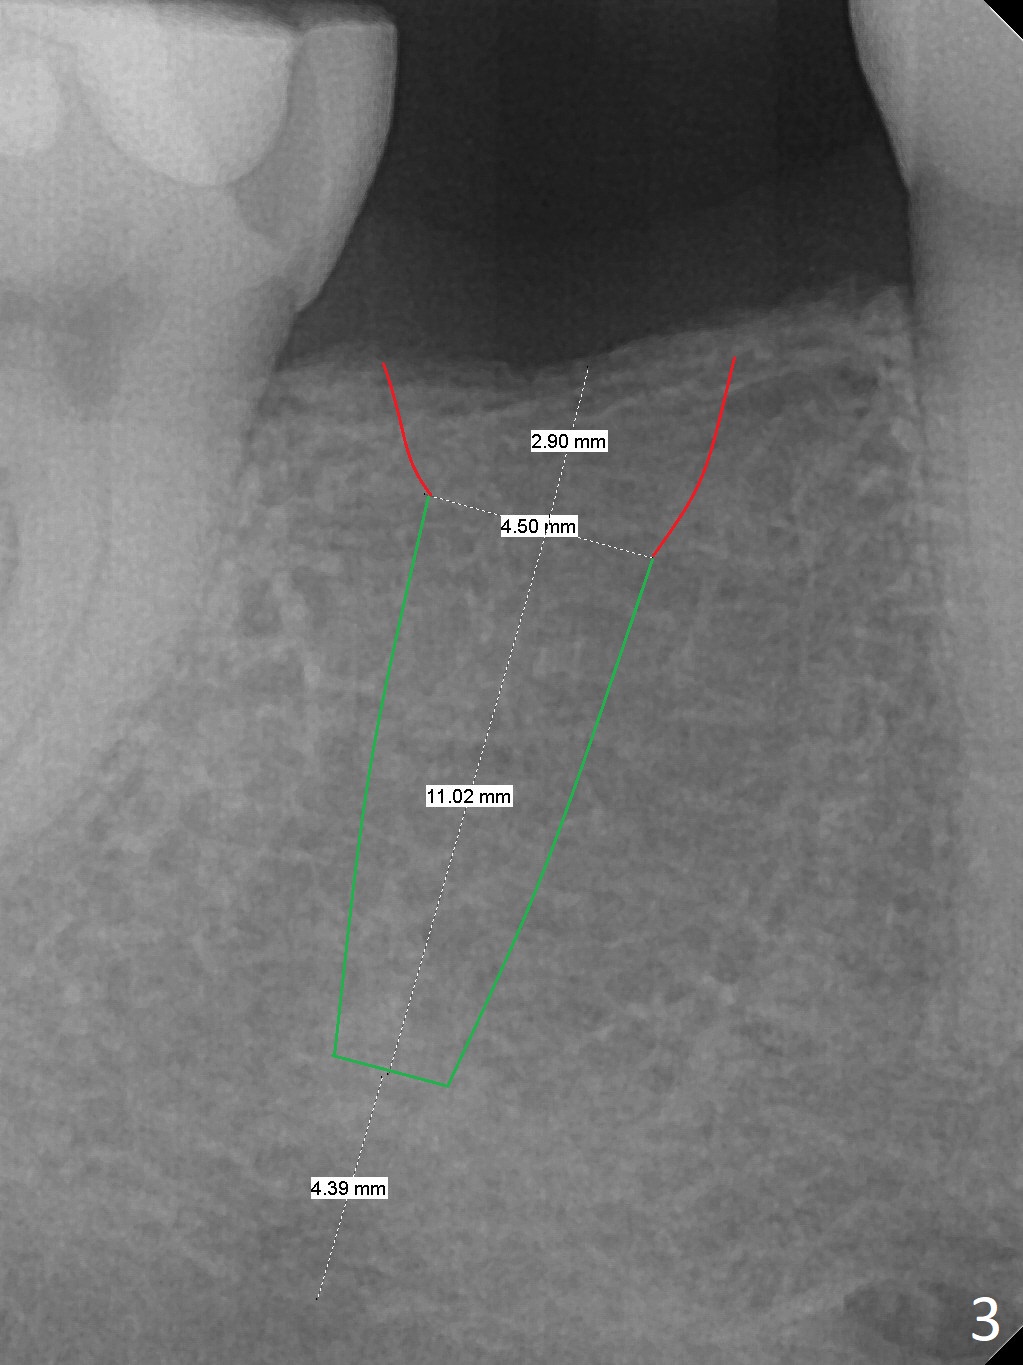

A 51-year-old man has a pyramidal ridge at #30 (Fig.1) with mild supraeruption of the opposing tooth (Fig.2 arrow). Ridge reduction will be done (Fig.3 red curved lines) prior to Bicon implant placement (green). A healing abutment is to be placed, followed by periodontal dressing.